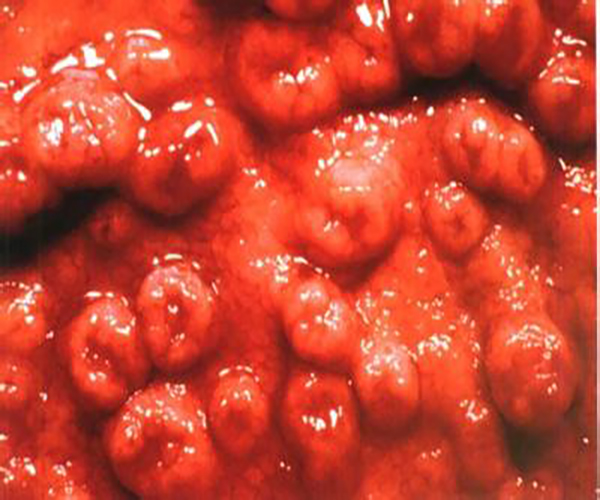

炎症性胃息肉

炎症胃息肉什麼症狀

炎症胃息肉

炎性胃息肉

炎性胃息肉切除

炎性胃息肉

炎性胃息肉的症狀表現